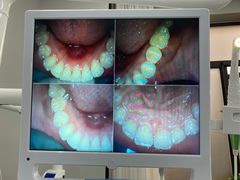

• 牙博士口腔品牌连锁(杨浦店)

• -牙博士口腔品牌连锁(杨浦店)